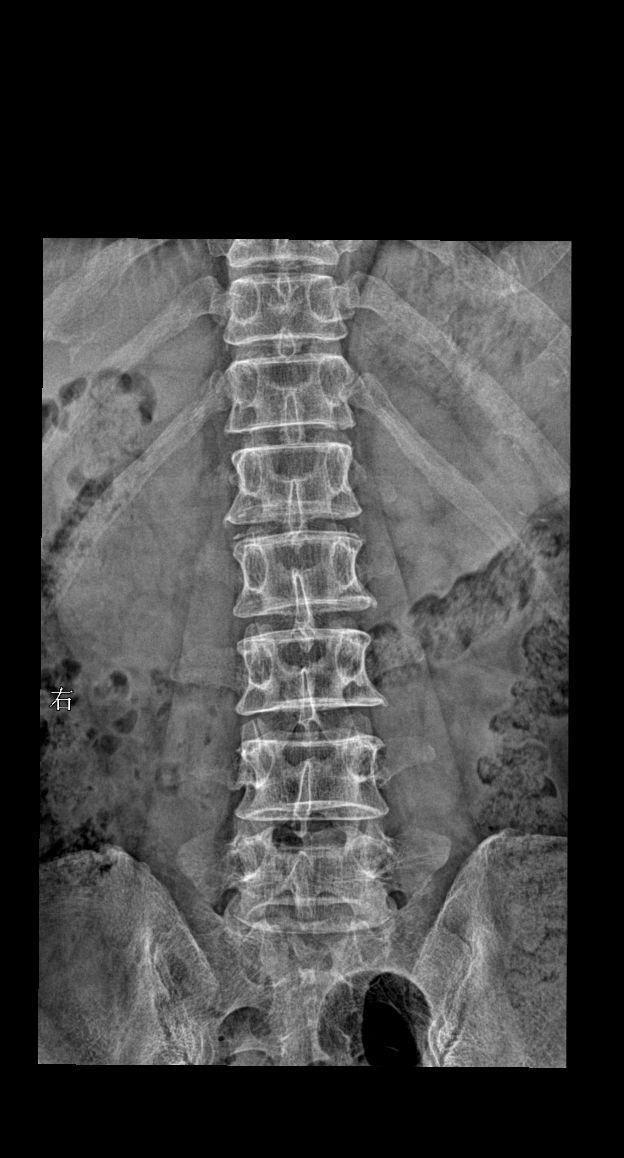

来了来了ok 大家踊跃参与讨论 患者主诉:男 52y 下肢麻木 酸疼 ...